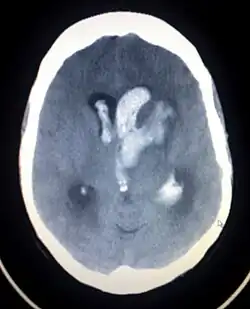

| An intracranial hemorrhage, one cause of altered level of consciousness | |